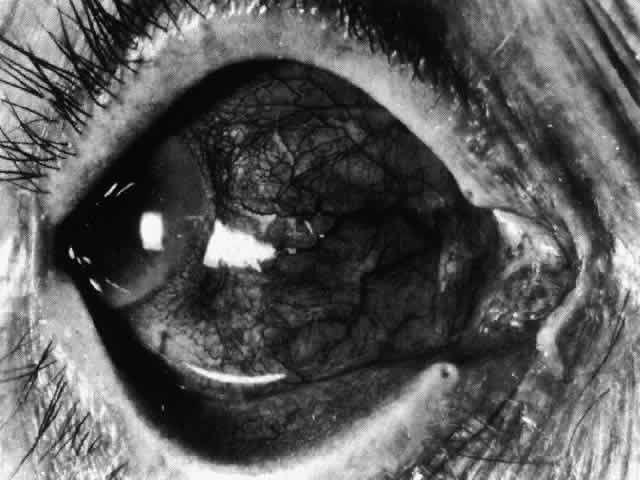

Necrotizing anterior scleritis without adjacent inflammation appears to be a well-defined condition with little relation in clinical features to necrotizing scleral disease, even though the pathology is similar and the final result is the same. Scleromalacia perforans is characterized by the almost total lack of any symptoms. It occurs almost exclusively in patients with long-standing polyarticular rheumatoid arthritis, the majority of whom are female (Figs. 49 and 50; Color Plate 1E).

Fig. 49. A white necrotic plaque developing in an area of sclera with practically no surrounding inflammation in a 60-year-old woman who had had Crohn's disease for 17 years.

Fig. 50. Scleromalacia perforans after treatment. The very thin sclera is covered by conjunctiva only and a few remaining large blood vessels. (Courtesy of Mr. HE Hobbs)

The anterior sclera loses its covering of episclera and develops an area of yellow-white necrotic slough over many months; this eventually separates or is absorbed, leaving the underlying choroid covered by either conjunctiva or nothing at all. As with necrotizing disease, the choroid does not bulge into this ectatic area; but unlike necrotizing disease, spontaneous healing of even small perforations is very limited once the necrotic tissue has been removed (see Fig. 50).

Fluorescein angiography is not helpful, except to indicate areas of vascular closure in an otherwise extremely thin, atrophic episcleral tissue.4 The formation of a sequestrum appears to be caused by arteriolar closure as opposed to the venular disease seen in the other forms of necrotizing scleritis.